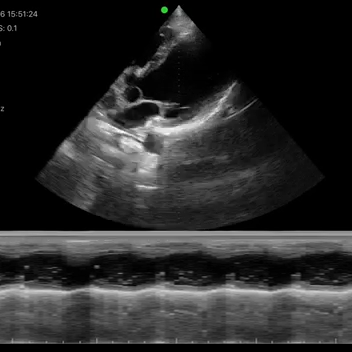

- Cardiac